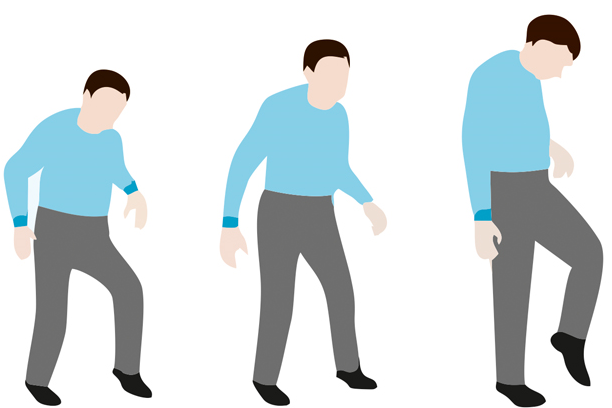

Parkinson’s disease is a progressive neurological disorder which leads to shaking (tremor), stiffness, slowness of daily activities, and difficulty with walking, balance, and coordination.

- Motor symptoms: They usually start on one side of body & usually spread to the other side of body as the disease progresses. These are:

- Slowness of speed of movements (bradykinesia)

- Stiffness of limbs (rigidity)

- Changes in posture, walking or balance difficulties

- Stage 1: One side of body is affected

- Stage 2: Both sides of body affected but balance remains intact

- Stage 2.5: Both sides of body affected with mild impairment of balance

- Stage 3: Bilateral disease with impaired balance but functioning intact.

- Stage 4: Moderate to severe bilateral disease; walking and standing difficult without help

- Stage 5: Wheelchair bound or bed-ridden